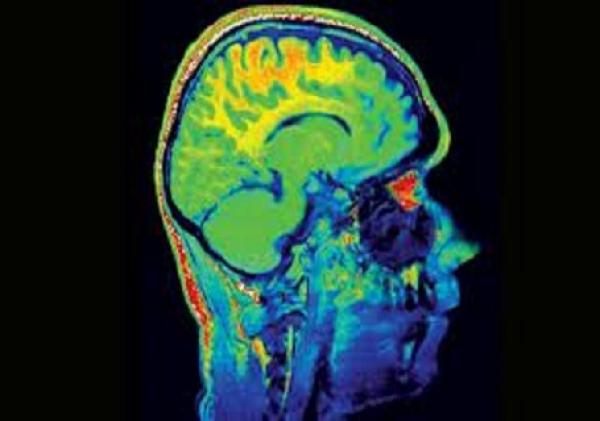

ابتكر خبراء بريطانيون في مجال الحاسوب وتكنولوجيا المعلومات لعبة الكترونية حديثة يمكنها أن تجعل المخ أصغر وأكثر شبابا بمعدل 7 سنوات وذلك عند ممارستها لمدة 10 ساعات لتأثير طويل قد يمتد الى عام كامل.

وأشار الباحثون الى أن العبة تعتمد على تدريب المخ ليتذكر المعلومات أثناء الاستمتاع بممارسة اللعب، وأظهرت الاختبارات بعد مرور عام من ممارسة مجموعة من النساء والرجال تصل أعمارهم الى 50 عاما لتلك اللعبة لمدة عشر ساعات، لم تتأثر ذاكرتهم بالتقدم في السن ، بل أصبحوا أكثر ذكاء وقدرة على التركيز.

وأضافوا أن في المتوسط كانت أدمغتهم ثلاث سنوات أصغر ، ولكن بعد اجراء اختبار واحد للسرعة والتركيز زادت قدرة الذاكرة والمخ وأصبحا أكثر شبابا بمعدل 7 سنوات.